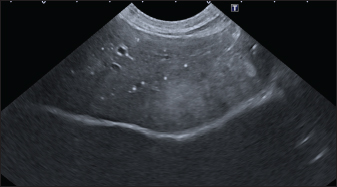

In the branched pattern, mineralizations were usually sub-centimetric or centimetric and they replicated the shape of the intrahepatic biliary tree (Fig. 3). Also in this case, sub-centimetric and centimetric IBTM determined a focal dilatation of the biliary ducts observed in 65.6% of dogs (21/32) (Fig. 4). In six of them (18.7%), we found millimetric IBTM randomly distributed in the liver.

Fig. 3. Ultrasound image of the liver showing sub-centimetric and centimetric IBM, generating acoustic shadow, with a branched pattern.

Fig. 4. Ultrasound image of the liver showing centimetric IBTM, generating acoustic shadow, with an aligned pattern. In the image, we can observe a focal dilation of the larger biliary duct, upstream and downstream to the calculi, because of the presence of the choleliths themselves.